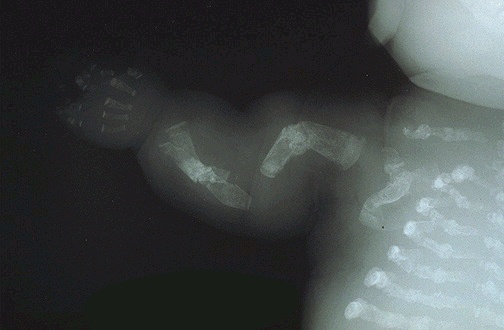

Image 7.3

Here is the radiographic appearance of the baby seen in image 7.2.